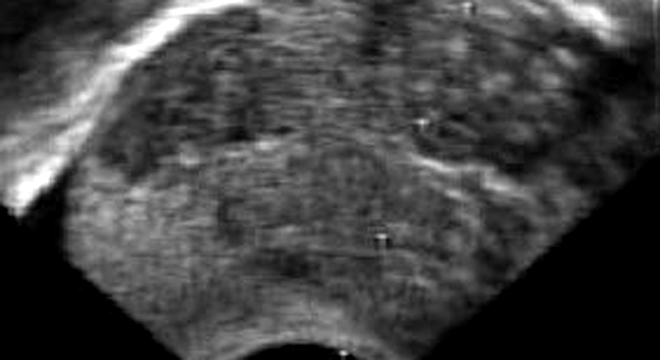

Hodenkrebs: Ultraschalluntersuchung

• Ultraschall, wenn nötig Gewebeproben